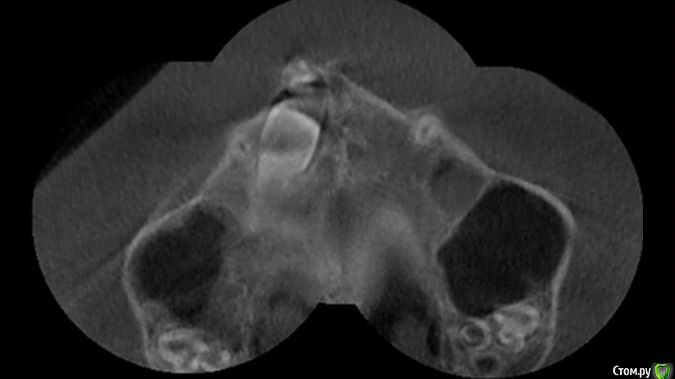

Kazankov.Egor Опубликовано 3 декабря, 2015 Поделиться Опубликовано 3 декабря, 2015 Ортодонт попросила открыть 11 зуб. Как поступить: одномоментно удалить Neo+доступ к 11 или Neo - время - доступ? После удаления Neo некоторое время будет пустота в зоне удаления (сгусток), в которую собираются двигать зуб. Это смущает. Скрины прилагаю. Размер Neo 12x11,5x10 mm. Ссылка на комментарий

Kazankov.Egor Опубликовано 3 декабря, 2015 Автор Поделиться Опубликовано 3 декабря, 2015 Тоже интересно, что скажут коллеги)) я такого сочетания не встречал, но моя тактика была бы такова: удалил эту загогулину (составная одонтома, или дентинома, если мне не изменяет память), заживление, раскрытие и вытягивание. Я не трус, но я боюсь))Просто я думаю о чем: По кт во фронтальном отделе очаг деструкции костной ткани, в остальных - четкая граница (капсула), удаление нео вызовет деструкцию оставшейся части компактной пластины, это сразу же приведёт к убыли костной ткани на фазе регенерации, может чем накрыть этот дефект? В НКР не смыслю, да и как показал опрос некоторых "мыслящих", практики движения зубов в такой кости не имеет никто. Ждём ответов Поднебесной))) Ссылка на комментарий